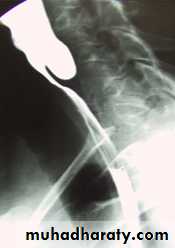

CausesEsophageal atresia

Types:• isolated atresia 8%

• Proximal fistula with distal atresia 1%

• Proximal atresia with distal fistula 85%

• Double fistula with intervening atresia 1%

• Isolated fistula [H-type] 4%